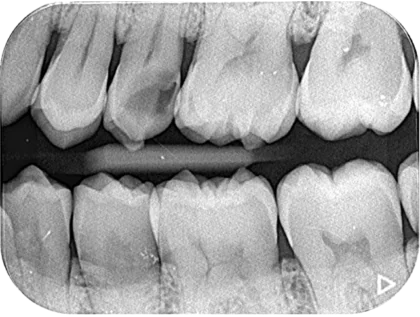

Case02

診断:う蝕 歯髄充血

Before

After(術後1年後)

| 主訴 | 左上の歯が欠けた。痛みはない。治療してほしい。 |

| 治療内容 | 診査したところ、25の歯に大きなう蝕(虫歯)があり、エナメル質の一部が欠けている状態。 歯髄には生活反応があり、自発痛や持続痛、咬合痛、など症状は認めなかった。レントゲン上でう蝕の範囲が広いことが確認でき、歯髄付近まで達していることから、V P Tによる歯髄の保存処置を計画し処置を行なった。術直後も自発痛など自覚症状は認められず、経過は良好。最終修復処置、一年後のレントゲン像でも根尖部に透過像などは認められず、歯根膜腔の拡大も認めないことから、経過は良好と確認できた。 |

| 治療期間 | VPT 来院回数1回 修復処置:レジン充填 来院回数1回 |

| リスク | 処置後、歯髄の炎症反応が起きる場合がある。 症状によっては、歯の神経の保存が困難となり抜髄になる。 |

| 費用 |

・初診料:15,000円 計:92,000円 |